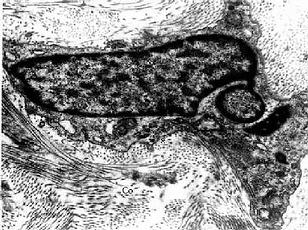

3.浆细胞 浆细胞(plasma cell)通常在疏松结缔组织内较少,而在病原菌或异性蛋白易于入侵的部位如消化道、呼吸道固有层结缔组织内及慢性炎症部位较多。细胞卵圆形或圆形,核圆形,多偏居细胞一侧,染色质成粗块状沿核膜内面呈辐射状排列。胞质丰富,嗜碱性,核旁有一浅染区(图3-2)。电镜下,胞质内含有大量平行排列的粗面内质网和游离的多核糖体。发达的高尔基复合体和中心体位于核旁浅染区内(图3-8,3-9)。

图3-9 猴浆细胞电镜像×10250

RER:粗面内质网

(白求恩医科大学尹昕、朱秀雄教授供图)

浆细胞具有合成、贮存与分泌抗体(antibody)即免疫球蛋白(immunoglobulin,Ig)的功能,参与体液免疫应答。浆细胞来源于B淋巴细胞。在抗原的反复刺激下,B淋巴细胞增殖、分化,转变为浆细胞,产生抗体。抗体能特异性地中和、消除抗原。